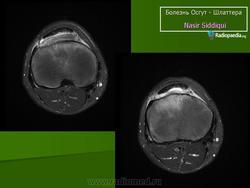

На рентгенограмме выявляются признаки фрагментации бугорка болылеберцовой кости.

На рентгенограмме отек мягких тканей, утолщение хряща, покрывающего бугристость спереди, фрагментация бугристости

В оценке рентгенологических признаков болезни Шлаттера необходимо учитывать большое число вариантов нормальной оссификации апофиза большеберцовой кости, разный ее характер справа и слева [Рейнберг С. А., 1964; Радулеску А., 1967]. Поэтому диагностику основывают на данных клиники (боль, припухлость) и несоответствии между значительным выбуханием хряща бугристости и меньшей ее величиной на рентгенограмме.